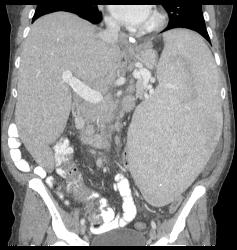

Splenomegaly With Portal Hypertension and Nodes in the Porta